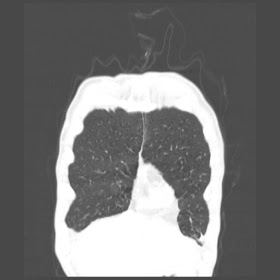

A 52 Years old man suffering with chest pain since 3 years

For seen patient record file please click here

HRCT Chest